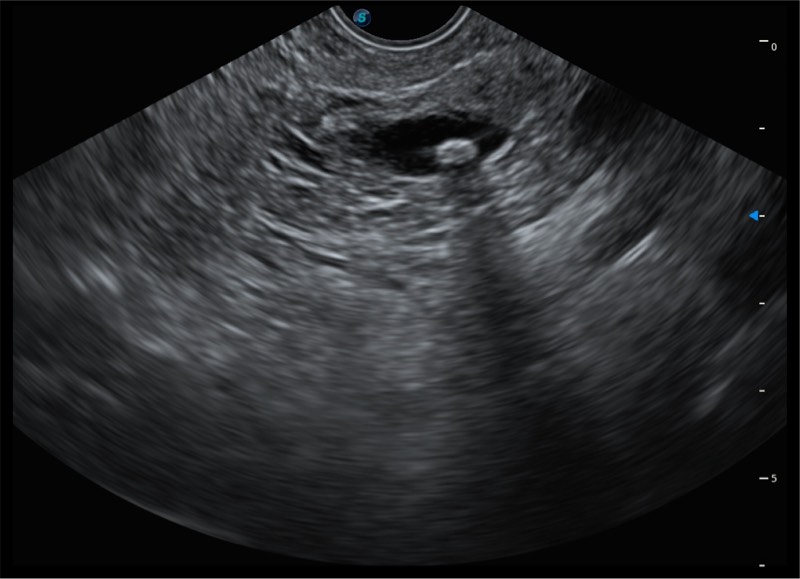

搭载百万级CMOS成像技术

及自主研发凸阵换能器,

可呈现优质的内镜和超声画面

基于二十年的超声技术积累,银河集团官网提供了最新一代的独立超声主机,在提供高质量图像的同时满足多学科使用。具备常见多普勒技术并提供弹性成像、声学造影等高端影像技术。新一代传感器具有更强的抗干扰能力并减少图像伪影。

4-12MHZ宽频输出